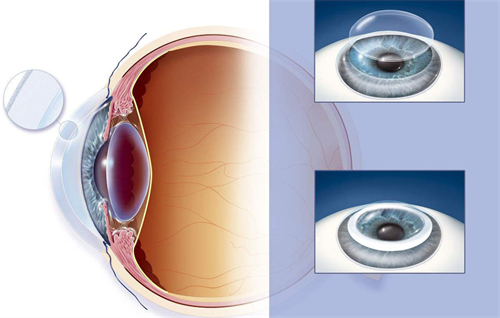

其他眼病:复杂白内障、青光眼、角膜炎等

小创口玻璃体切割术:使用25G/27G超小创口系统,创伤小、修复快

复杂性视网膜脱离复位术:成功概率高,术后视力修复良好

黄斑手术:包括黄斑前膜剥除、黄斑裂孔修复等

眼内注药术:治疗黄斑水肿、新生血管等